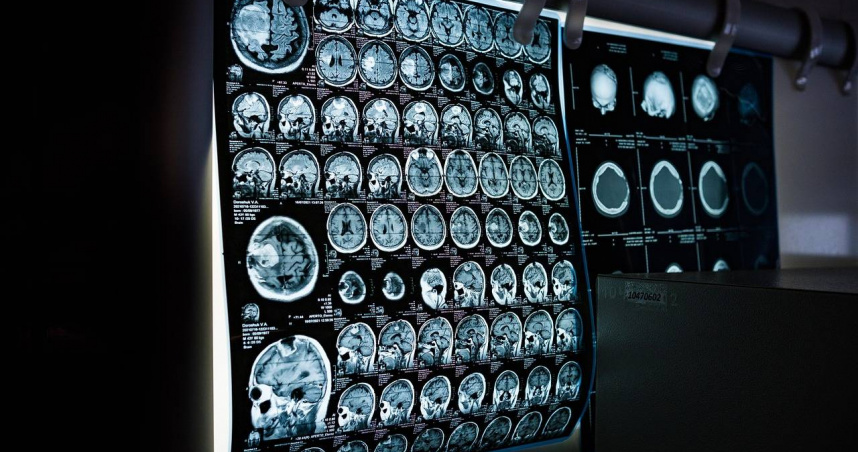

中國一名男子參加公司體檢沒異常,1年半後卻診斷出癌症晚期。(示意圖/翻攝自pixabay)

中國一名男子參加公司的體檢,結果顯示肺部沒異常,1年半後卻確診癌症晚期,他認為公司應該承擔賠償責任,因此提出法律訴訟。經過審理後,結果也出爐了。

陳男在訴訟過程中申請司法鑑定,司法鑒定中心認為早期肺癌尤其是周圍性肺癌往往無任何症狀,多是進行電腦斷層攝影才發現,只有在病變早期才能獲得較好療效。

司法鑒定中心查閱陳男第一次體檢胸部電腦斷層攝影,顯示肺部存在一實質性結節,且再次體檢有增大、圓凸跡象,可推斷為同一病理分期,因此認定體檢機構存在漏診過錯,建議承擔85~95%的責任。